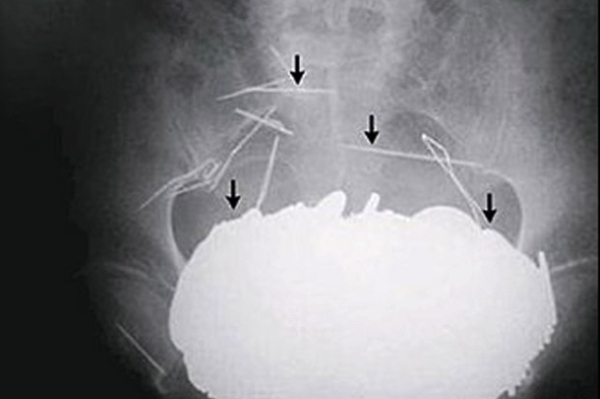

Неожиданные находки в теле человека: ТОП-20 фото

Люди порой поражают медиков странными вкусовыми пристрастиями и удивляют неожиданными вещами, которые по разным причинам оказались в человеческом теле и доступны взору только на рентгеновских снимках. Смотри подборку самых неожиданных находок в человеческом организме

Некоторые люди умудрились удивить медиков странными находками, обнаружившимися в их желудках и телах на рентгеновских снимках. Следует отметить, что многие предметы оказались в человеческом организме волей случая, но некоторые из них - по воле их носителей.